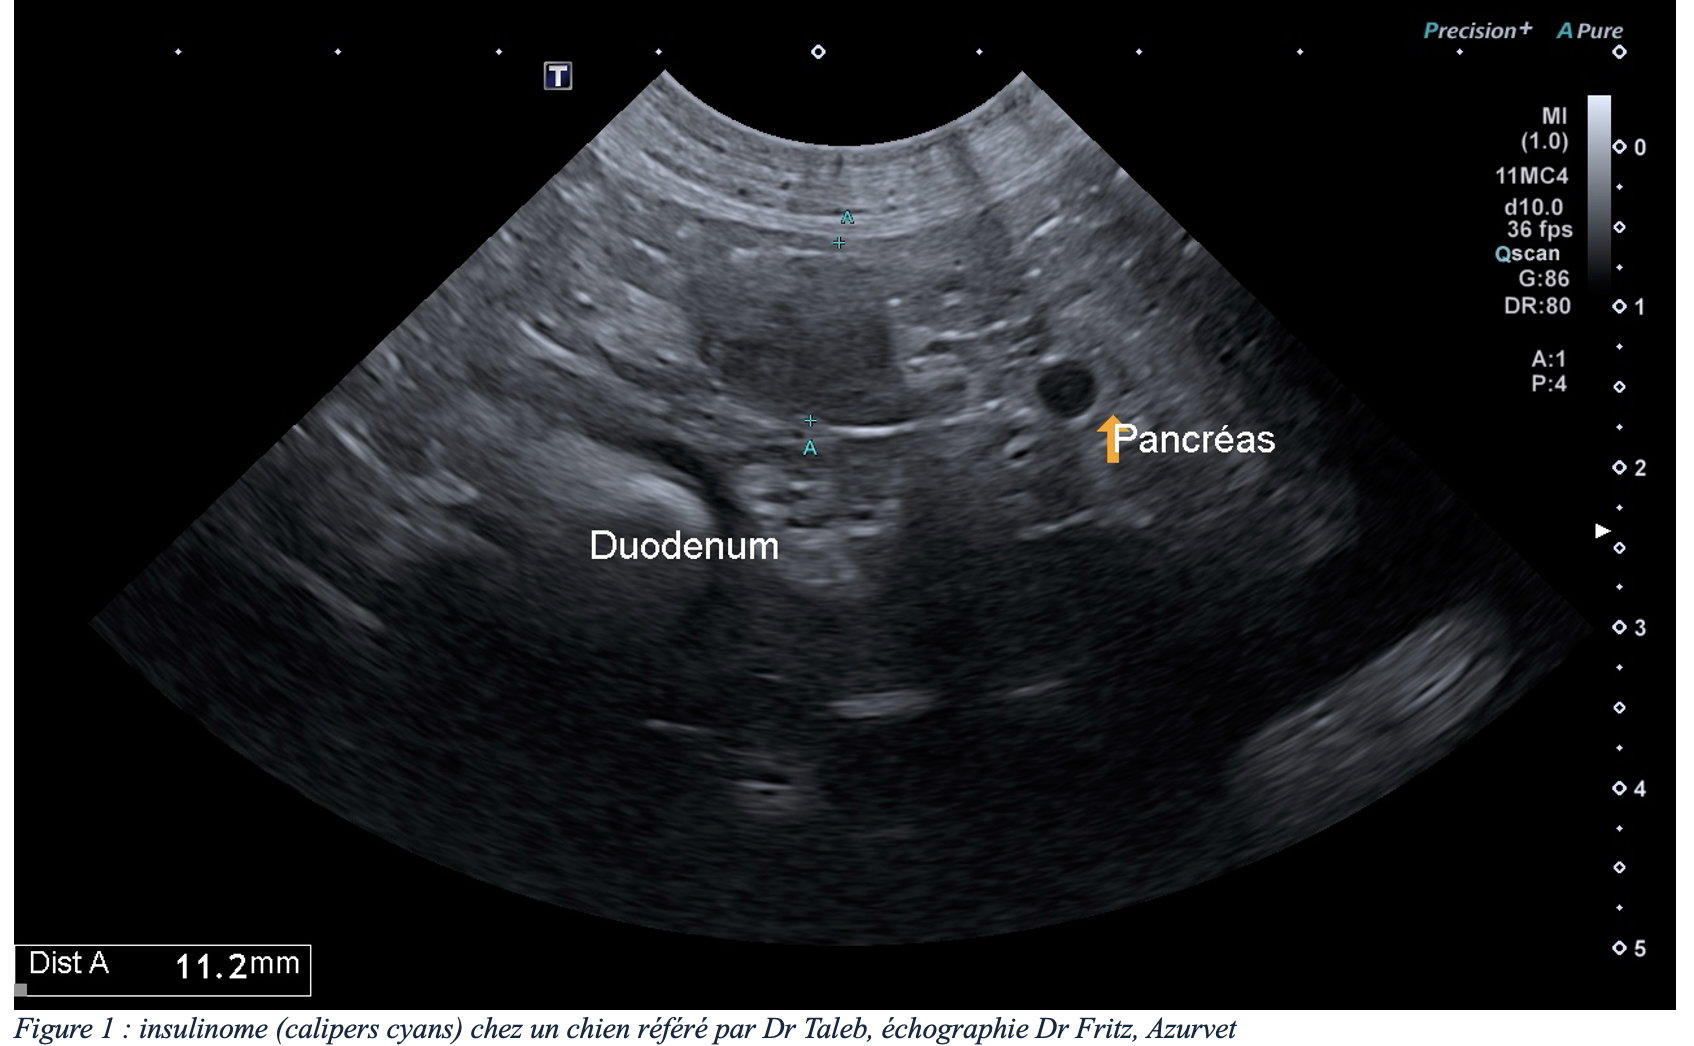

L’échographie est un examen de première intention pour l’exploration d’un insulinome. La sensibilité de l’échographie dépend de l’expérience du manipulateur, mais aussi de la conformation de l’animal (l’examen du pancréas est limité sur des chiens de grande taille et/ou avec cage thoracique profonde). Un insulinome peut se présenter dans la plupart des cas comme un nodule unique hypoéchogène de taille variable (figure 1), et de façon moins fréquente comme des nodules multiples ou une zone irrégulière plus diffuse du pancréas (2) – noter que ces lésions ne sont pas spécifiques d’un insulinome et que tout autre nodule bénin ou malin du pancréas peut avoir cette apparence et donc que la suspicion clinique/biologique est cruciale. L’échographie permet également une évaluation des nœuds lymphatiques et du foie pour un premier bilan d’extension.